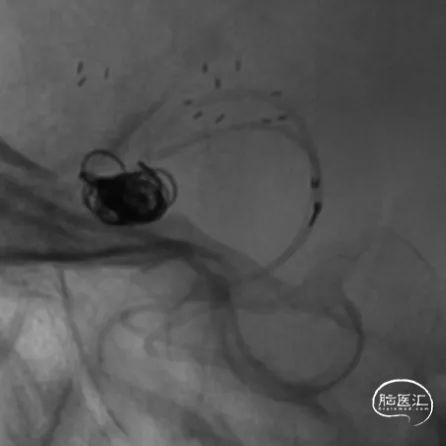

工作位术前造影及路图。

Synchro10微导丝引导两条SL-10微导管分别超选入右侧大脑中动脉下干(红管)和上干(蓝管)。

将3mm*21mm Atlas支架通过上干微导管输送到位,对位准确后,通过微导管成功释放。

释放完第一枚支架的SL-10微导管(蓝管)留在M1水平段不撤出,然后用微导丝将其引导穿过第一枚Atlas支架的网眼超选入MCA下干的另一分支,微导丝及微导管穿网眼过程中Atlas支架稳定。成功穿网眼建立第二枚支架通路后,将备用的SL-10微导管(红管)轻轻后撤,管头正好从下干落入动脉瘤腔内,留待填塞弹簧圈用。

经下干的SL-10微导管释放第二枚Atlas支架,形成“Y”型支架形态,充分保护上下两干,Atlas支架打开顺畅,影像下可清晰看到两端标记点完全打开。第二枚支架释放完毕后,顺势将该SL-10微导管经支架网眼顺利超选入瘤腔,拟双微管填塞。经一根SL-10微导管释放第一枚Target XL 4mm*12cm弹簧圈进行成篮。